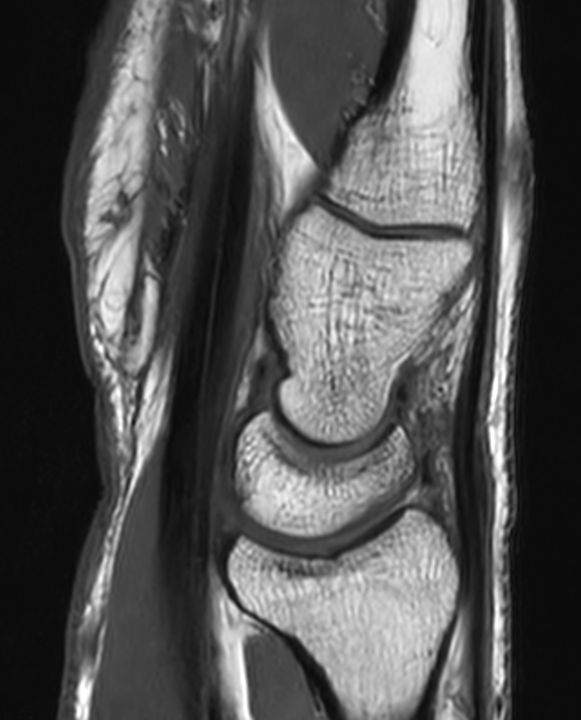

Sagittal T1w TSE